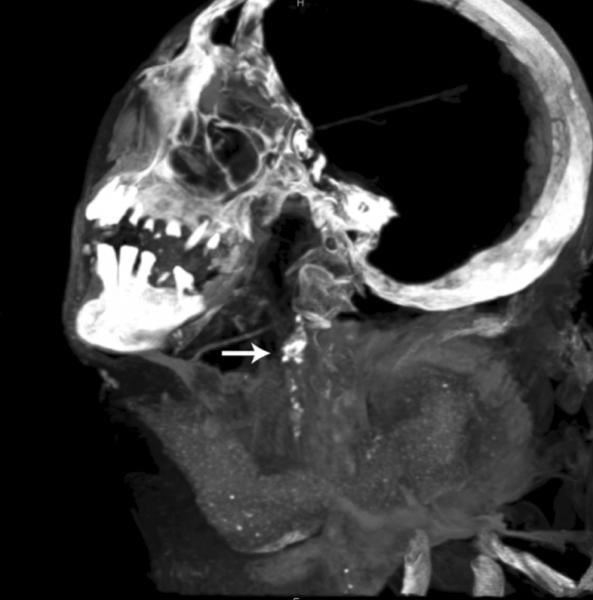

CT scan showing Egyptian mummy with calcified aortic bifurcation.

While the HORUS Study has previously reported atherosclerotic vascular calcifications on computed tomography (CT) scans in ancient Egyptians, the HORUS team’s new study was to compare patterns and demographic characteristics of this disease among Egyptians from both ancient and modern eras.[1] The scans at the Museum of Egyptian Antiquities were performed using a Siemens Somatom Emotion 16-slice CT system. The authors compared the presence and extent of vascular calcifications from whole-body CT scans performed on 178 modern Egyptians from Cairo undergoing positron emission tomography (PET)/CT for cancer staging to CT scans of 76 Egyptian mummies (3100 BC to 364 AD). Patients undergoing cancer staging were selected for the study because these scans had already been completed for this group of patients as part of their cancer care.

The mean age of the modern Egyptian group was 52 years (range 14 to 84) versus estimated age at death of ancient Egyptian mummies 36 years (range 4 to 60). Vascular calcification (evidence of atherosclerosis) was detected in 108 of 178 (61%) of modern patients versus 26 of 76 (38%) of mummies, with vascular calcifications on CT strongly correlated to age in both groups. In addition, the severity of disease by number of involved arterial beds also correlated to age, and there was a very similar pattern between the two groups.